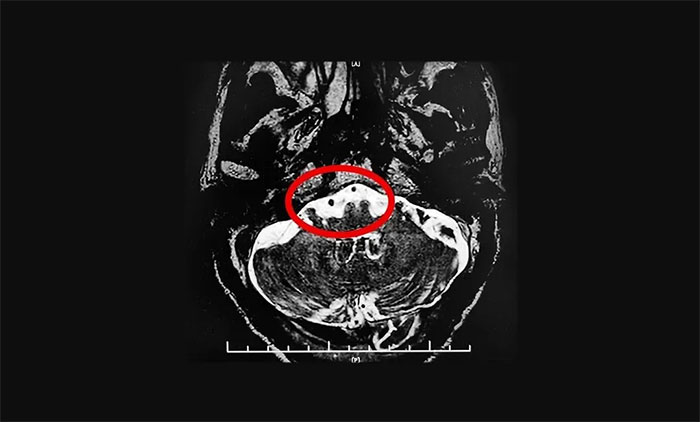

▲双侧三叉神经与周围小血管关系密切(左侧接触显著)

在办理入院手续后,杨忠旭教授详细了解了张老汉的病史资料,并为其申请了三叉神经MRTA平扫+增强等相关检查。结合影像资料,杨忠旭教授指出患者双侧三叉神经与周围小血管关系密切(左侧接触显著),手术指征明显,未见明显手术禁忌症。